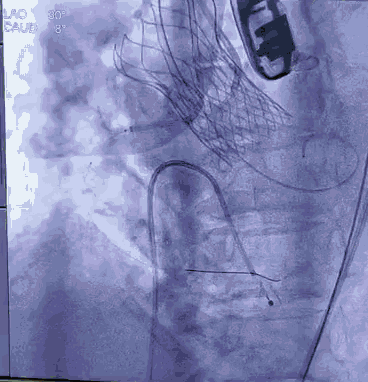

顺利跨瓣,测得跨瓣压差62mmHg。送20mm球囊扩张主动脉瓣,经右桡动脉猪尾导管造影,冠脉切线位未见右冠脉显影。为策安全,决定对RCA行冠脉保护,送JR4导管及guidzila和3.5球囊行冠脉保护。置入24mm微创 vitaflow瓣膜标准位释放。复查造影显示少量主动脉瓣返流,左右冠显示良好,撤除右冠保护。术后测压差为10mmHg。缝合双侧股动脉。术后恢复良好,次日转回普通病房,顺利出院。